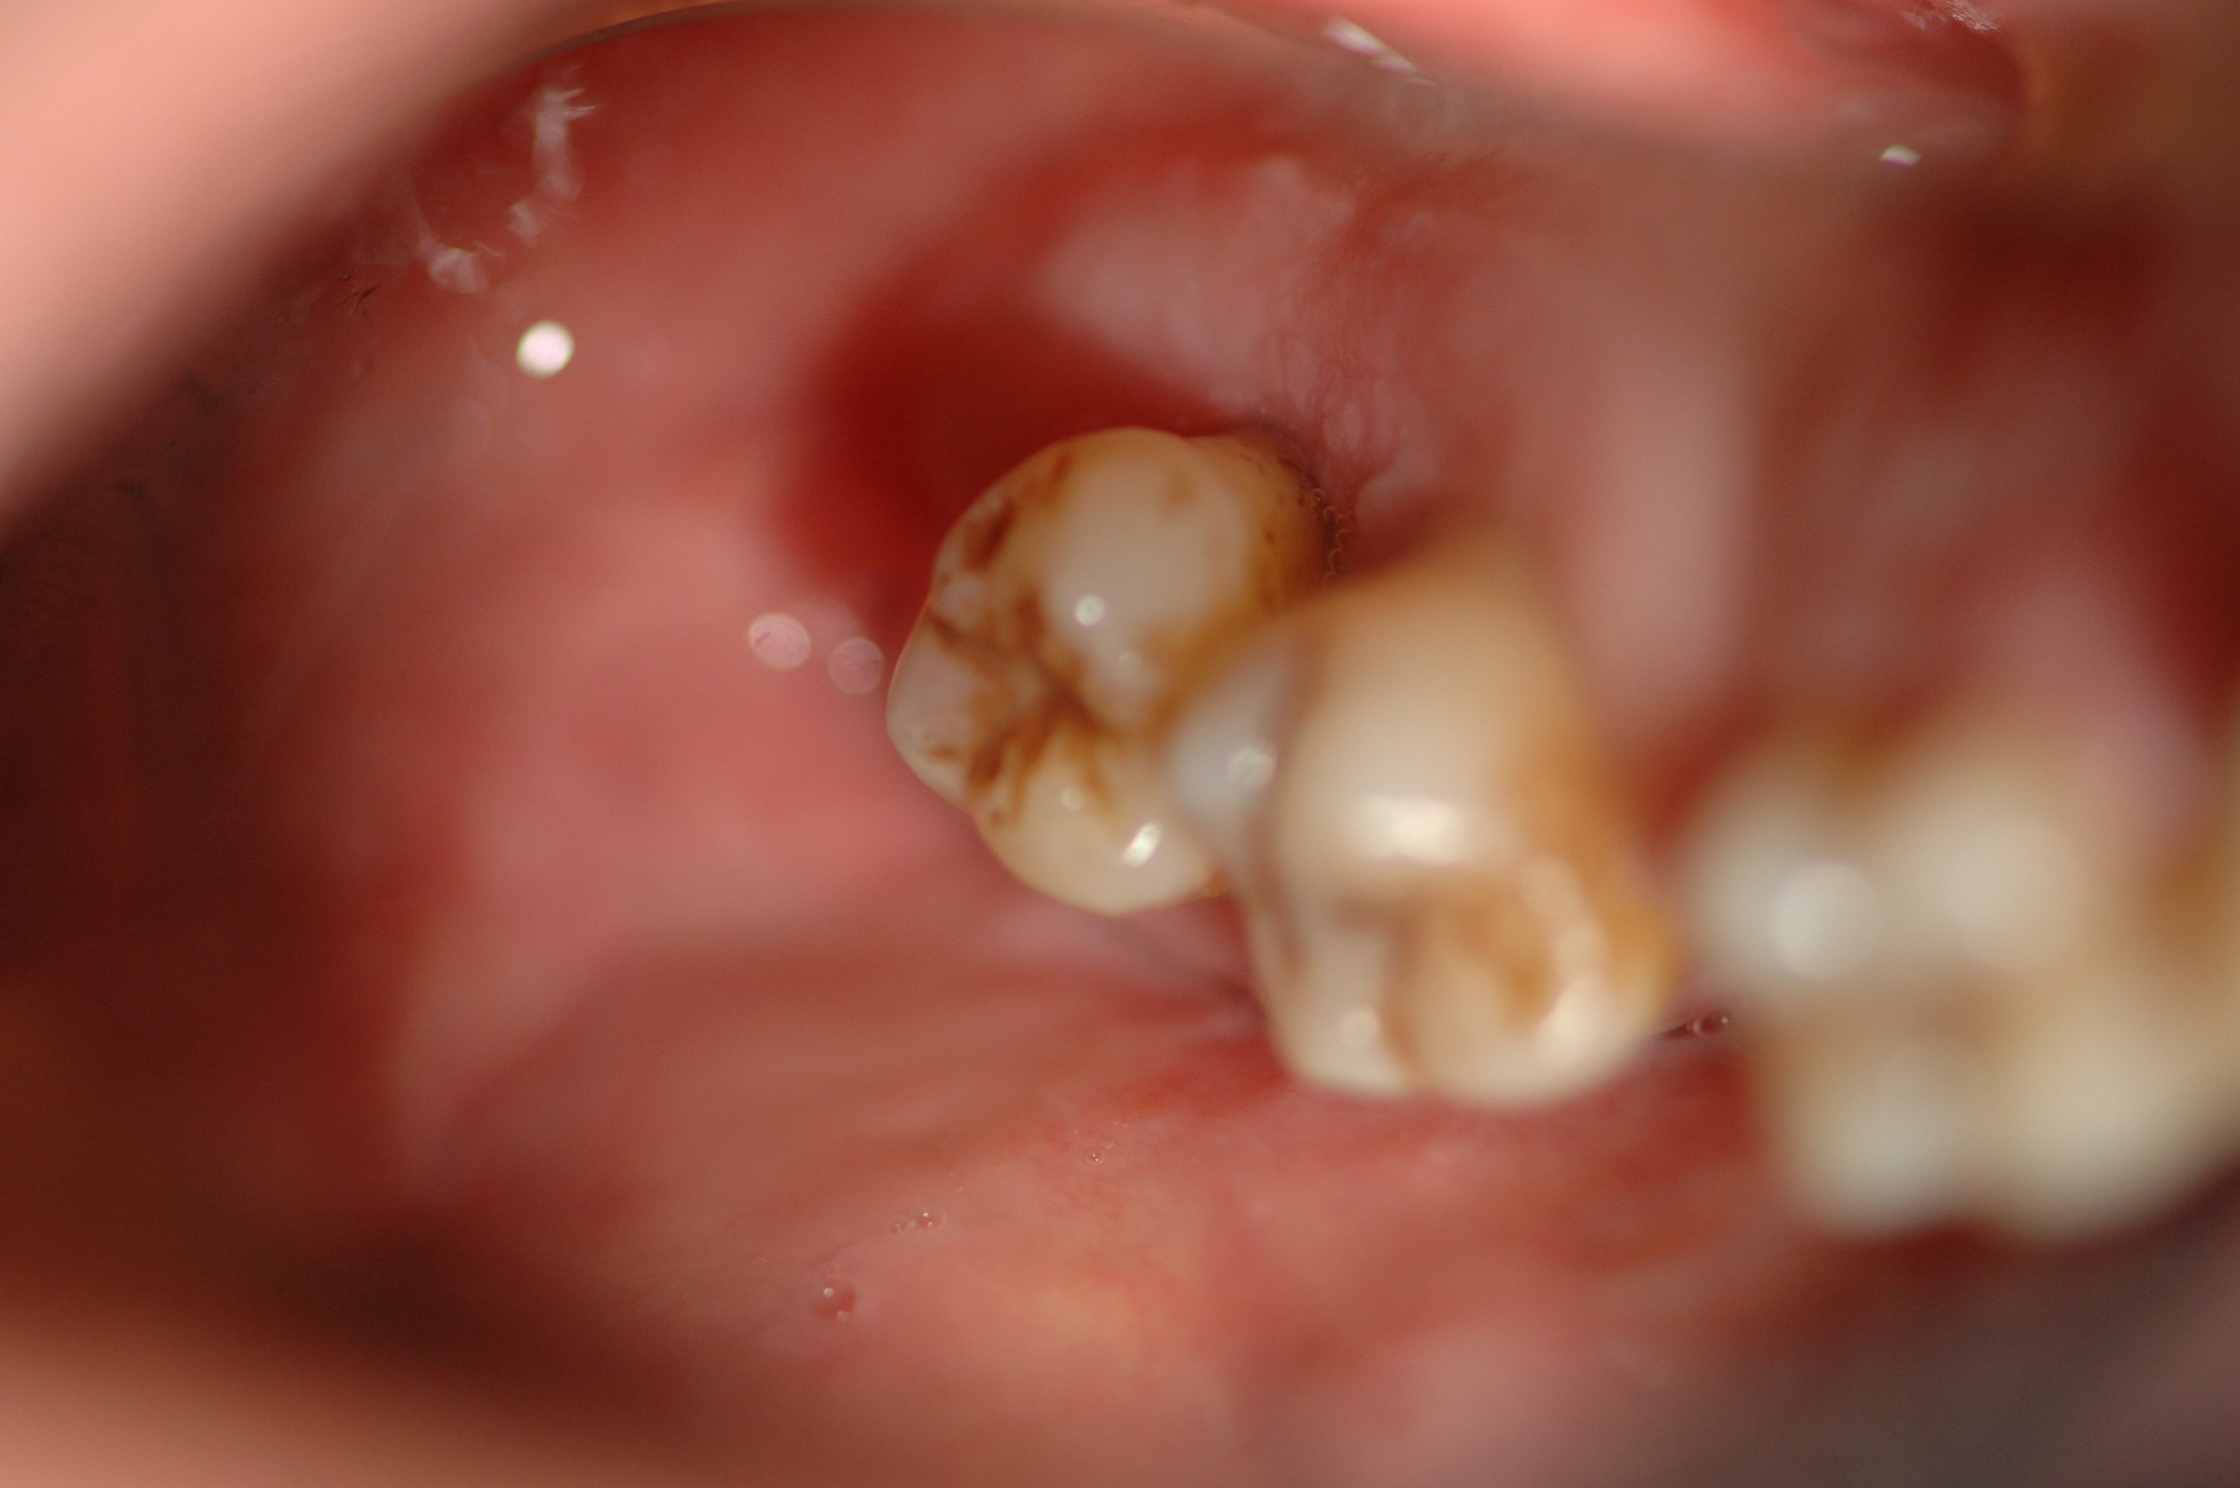

Publié le 05/09/2016Patient présentant des hyperplasies très volumineuses au palais, des deux côtés. Ces hyperplasies sont à l’origine de fausses poches.

Le patient a une gêne à l’alimentation, spécialement à la déglutition. La respiration est aussi perturbée.